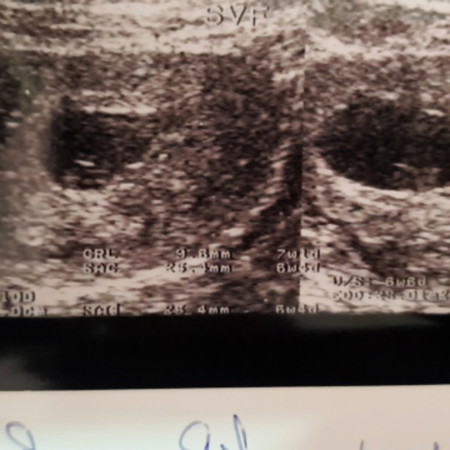

ถ้านับวันตามประจำเดือนอายุครรภ์ตอนนี้ได้ 10week 6day แต่พาหมอซาวด์ออกมาแค่ 7week 1day หมอก็บอกว่าเคลื่อนเยอะ อยากจะถามว่าใครเคยเป็นเหมือนเราบ้างคะ